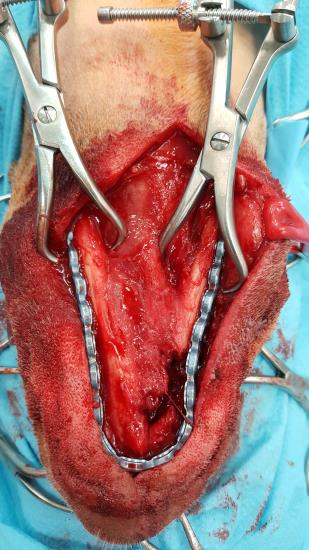

After 4 weeks Mac was presented for jaw reconstruction. At this point, jaw function was good, but both mandibles were unstable and there was evidence of impaired function when picking up food. A ventral approach was made to both mandibles. A pre-contoured 20 hole Synthes 2.4m reconstruction plate was fixed to the mandible.

Fig. 2: Intraoperative picture showing a pre-contoured 20 hole Synthes 2.4m reconstruction plate fixed to the mandible. Note the defect caused by the resection of an acanthomatous ameloblastoma.

Mac’s occlusion was evaluated at this point and it was normal. A 2.7 cm section of Mastergraft compression resistant matrix, impregnated with BMP (Inductos – Medtronic) at 0.5mg/ml was placed in the defect and a tight soft tissue capsule was created to stabilise the graft.